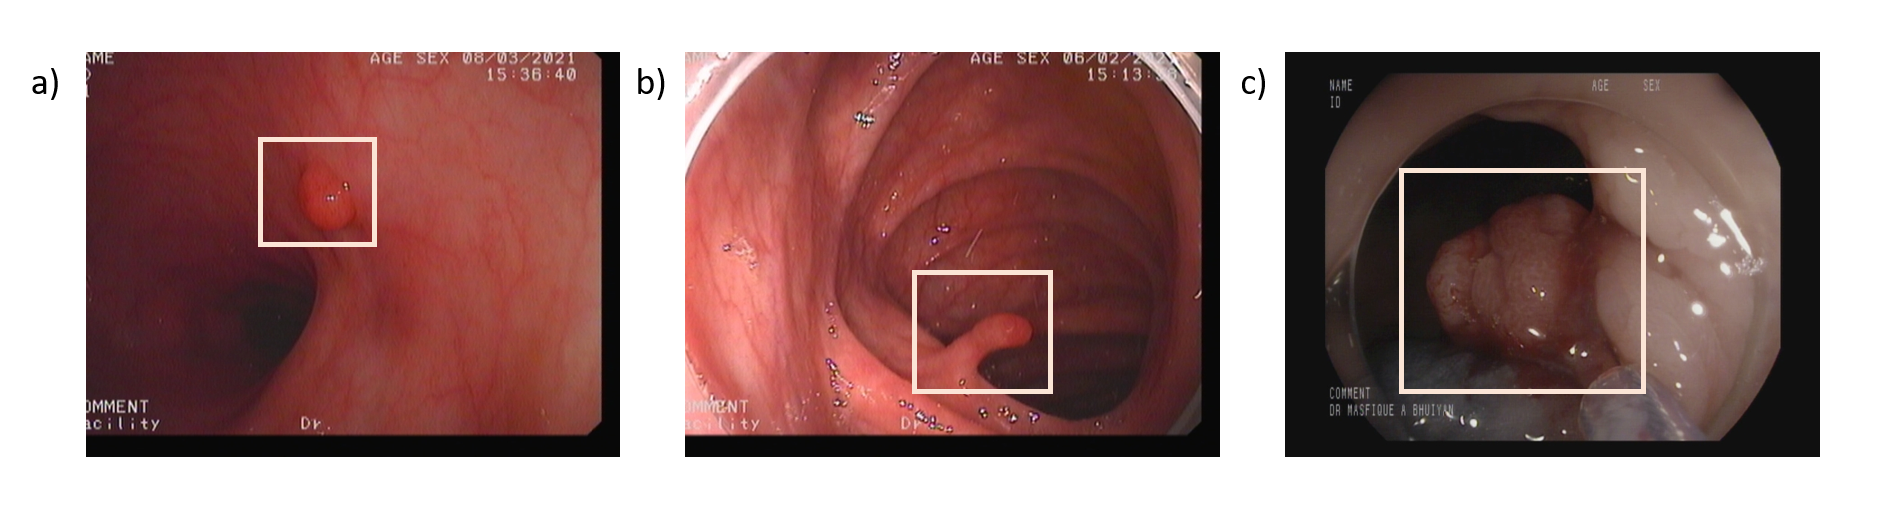

Refer to caption

Figure 1: Examples of colorectal polyp morphologies observed during colonoscopy. (a) Sessile polyp lying flat against the colonic mucosa, making detection more challenging.(b, c) Pedunculated polyps with stalk-like structures protruding from the mucosal surface.

Colorectal polyps generally exhibit two distinct morphologies: sessile (flat) and pedunculated (stalked) as shown in Fig.1. Sessile polyps, which are now recognized as more prevalent than once believed, are particularly challenging to detect during colorectal cancer screening due to their flat structure that closely adheres to the mucosal surface of the colon. In contrast, pedunculated polyps resemble a mushroom-like structure, protruding from the mucosal lining and connected by a narrow, elongated stalk [13] .